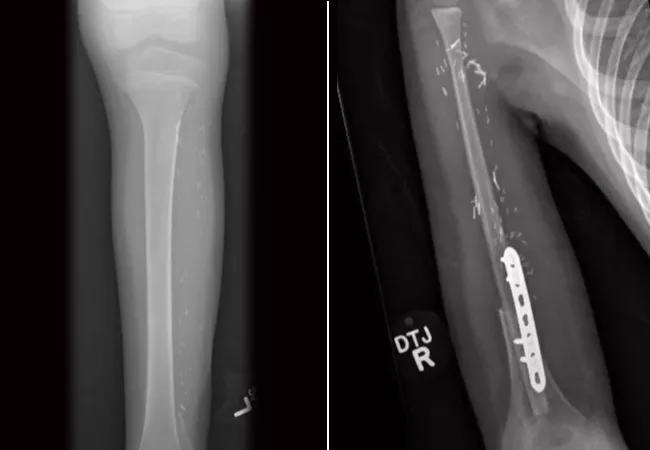

The Leg Bone’s Connected to the Arm Bone: Surgeons Use Fibula to Reconstruct Humerus in Unique Pediatric Sarcoma Case

This was certainly true in a recent case when a 5-year-old patient presented to Cleveland Clinic with substantial swelling in his right shoulder, his dominant arm. A thorough workup revealed that the patient had humeral osteosarcoma. The pediatric oncology team began chemotherapy immediately, and the tumor responded nicely over several months. Next, was Dr. Mesko’s challenge.

“The challenge of reconstruction was to provide this energetic, fun-loving 5-year-old with an arm that allowed his humerus and elbow to serve as a working platform for his hand while saving all of the important nerves and blood vessels in his arm, giving him a chance at some form of growth in that arm,” he explains.

Dr. Mesko shares more details about this case, including a collaboration with Graham Schwarz, MD, of Cleveland Clinic’s Department of Plastic Surgery. The teams worked together, utilizing a free fibula transplant technique to reconstruct the patient’s humerus. “At three months, the patient was feeling like himself again, and the real challenge was trying to keep a 5-year-old down.” Learn how this particular challenge was failed, and more about this unique case in the video below: